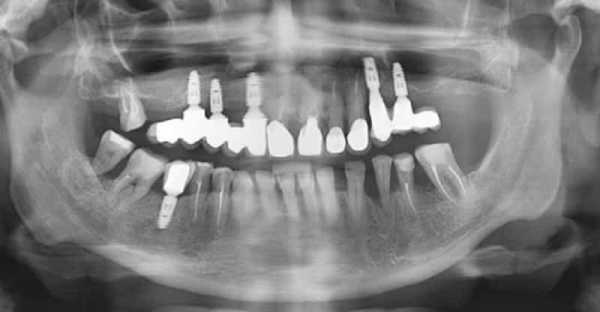

На следующем этапе проводятся подготовительные мероприятия. Врач должен устранить все кариозные полости и провести терапию воспалительных забеливаний во рту. Также удаляются старые протезы и коронки. Обязательное подготовительное мероприятие – панорамный снимок челюсти.

Панорамный снимок челюсти в трехмерной проекции

Исследование необходимо для выявления патологий, которые являются противопоказанием для установки искусственных зубов. С помощью рентгена можно увидеть наличие доброкачественных новообразований у корней зуба – кист и гранулем. По снимкам врач может оценить особенности строения челюсти и ее толщину на различных участках. Эти нюансы дают возможность с точностью распланировать предстоящую операцию.